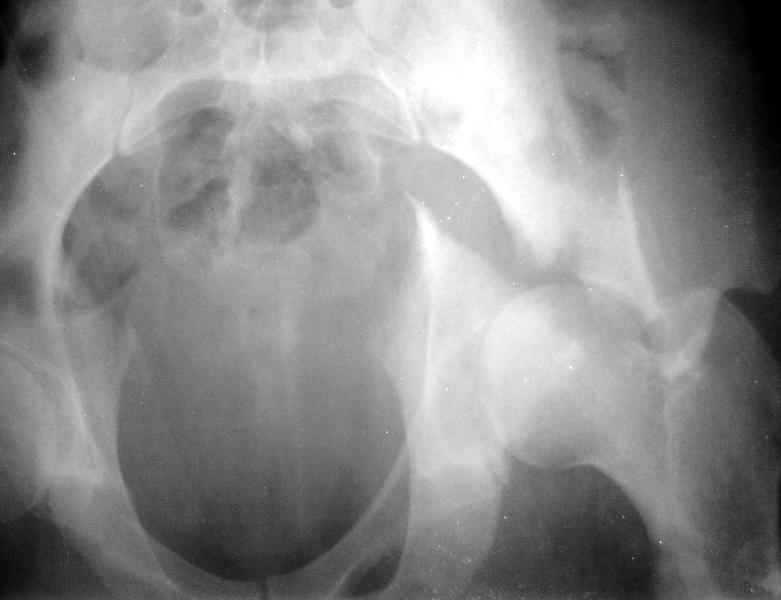

Для уточнения диагноза необходим обзорный снимок таза и Judet проекции. Судя по присланной короткой рентгенограмме, один из компонентов перелома - отрыв свода, точно имеется ступенеобразная деформация нагружаемой поверхности и без открытой репозиции ничего хорошего не будет. Если в ближайшую неделю восстановительная опеперация не будет сделана, то лучше потом и не пытаться, а ждать сращения бедра для эндопротеза.

Сегодня на приеме был пациент, чьи начальный снимок напомнил обсуждаемый сейчас (см. выше). Снимки в других проекциях, показывающие истинный характер повреждения, ниже. Это inlet проекция (вход в таз) и запирательная проекция Judet.

Травма 17 ноября 2002 г., поступил к нам 1 декабря, оперирован 8-го - открытая репозиция, остеосинтез пластинками и винтами. Учитывая повреждение переднего полукольца справа, и крестца и крестцово-подвздошного сочленения слева, наложили аппарат на 2 месяца.

Для экономии места привожу интра- и послеоперационный обзорный снимок, без дополнительных проекций.